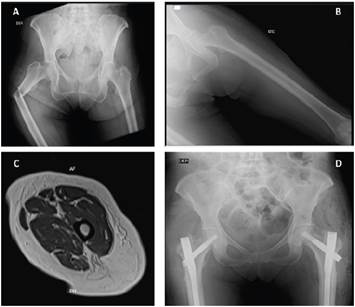

An x-ray of the pelvis and both femurs showed a displaced and angulated oblique fracture of the proximal third of the femur, minimally comminuted (as seen in Figure 1A), and V-shaped periosteal thickening, shown in Figures 1B and 1C.

Blood chemistries showed vitamin D insufficiency (Table 1). Seven days after admission she underwent fracture repair with a cephalomedullary nail, and eight days after this procedure she underwent prophylactic contralateral cephalomedullary nailing (images available in Figure 1D), and was discharged that same day with a prescription for physical rehabilitation and Teriparatide.

The diagnostic criteria for atypical fractures were defined in 2010 18 and reaffirmed in 2014 in the second report of the American Society for Bone and Mineral Research working group. These included the location in the femoral diaphysis, absent or minimal trauma, the lineal nature of the fracture, minimally comminuted fractures, and V-shaped periosteal and endosteal thickening 19. Our patient's symptoms occurred three months before the atypical fracture, with a minimally comminuted fracture point in the proximal third of the right femur, no prior trauma, and periosteal and endosteal thickening seen on imaging (Figures 1B and 1C), which enabled a clinical and imaging diagnosis of the condition in this case. Although atypical fractures due to the use of bisphosphonates and other pharmacological treatments used to reduce the risk of osteoporotic fractures are rare, the likelihood of occurrence is related to antiresorptive treatment lasting more than four or five years 14. Our patient had received the treatment for five years, with a year-long pause and treatment resumption in 2023.

Figure 1 A: a pelvic x-ray showing an oblique, displaced, angulated fracture of the proximal third of the femur. B: an x-ray of the left femur shows V-shaped periosteal thickening. C: nuclear magnetic resonance imaging of the femur showing regular, circumferential, hypointense cortical thickening of up to 8 mm in the diaphysis, proximal metaphysis and distal metaphysis, in all sequences, without expansile lesions or cortical destruction. D: a pelvic x-ray showing osteosynthesis material in both femurs.

Surgical management of bisphosphonate-related atypical fractures should be approached with caution and careful planning. In addition, treatment of the contralateral side mainly depends on the patient's symptoms or lack of symptoms and the femoral x-ray (17). Our patient had radiographic signs in the contralateral femur that suggested microfractures (Figures 1B and 1C). Therefore, although the decision to perform surgery to correct the fracture point was made quickly, there was no consensus at first on whether to perform surgery on the contralateral femur. This discussion involved evidence that was still under construction and intense debate, which therefore required a multidisciplinary team of geriatricians, orthopedic surgeons, and rehabilitation professionals to determine that the insertion of a cephalomedullary nail in the contralateral femur was the best strategy to prevent a future fracture (Figure 1C).